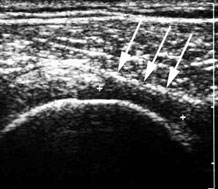

Besonders wertvoll ist diese Untersuchung für die frühzeitige Diagnose einer Dysplasie(Unterentwicklung) der Hüftgelenke beim Säugling, was in Deutschland eine Routineuntersuchung darstellt, in Griechenland aber fast unbekannt ist. Durch die frühzeitige Diagnose kann wertvolle Zeit gewonnen werden, da durch den früheren Therapiebeginn meist ein operativer Eingriff vermieden werden kann.